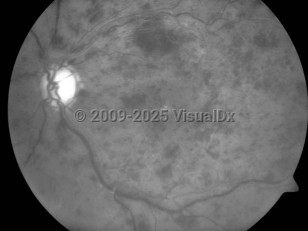

Central retinal vein occlusion - External and Internal Eye

Central retinal vein occlusion (CRVO) is a potentially blinding subacute vascular occlusion of the eye. The prevalence of CRVO is between 0.1% and 0.4% in individuals who are aged 40 or older. Most patients have associated local or systemic disease, with systemic hypertension, diabetes mellitus, and open-angle glaucoma being the most common.

The occluded central vein can lead to intraretinal hemorrhage, exudation of fluid, varying levels of ischemia, and neovascular complications such as neovascular glaucoma. CRVO is commonly classified by severity into 2 forms: the nonischemic form of CRVO, which is milder and more common, and the ischemic form, which results in more severe retinal damage and vision loss. In ischemic CRVO, more than 90% of patients have vision of 20/400 or worse. One-third of patients with the nonischemic type progress to the ischemic type.

Iris neovascularization, which is associated with neovascular glaucoma, occurs in up to 60% of patients with the ischemic form, usually 3-5 months following the obstruction. The main risk factors for development of neovascular glaucoma after a CRVO are the extent of capillary nonperfusion, poor visual acuity, severe venous tortuosity, and retinal hemorrhage.